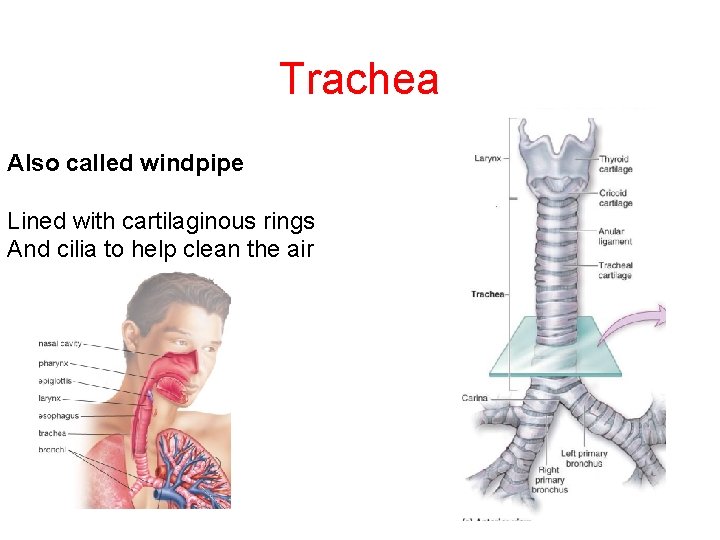

Trachea Also called windpipe Lined with cartilaginous rings And cilia to help clean the air